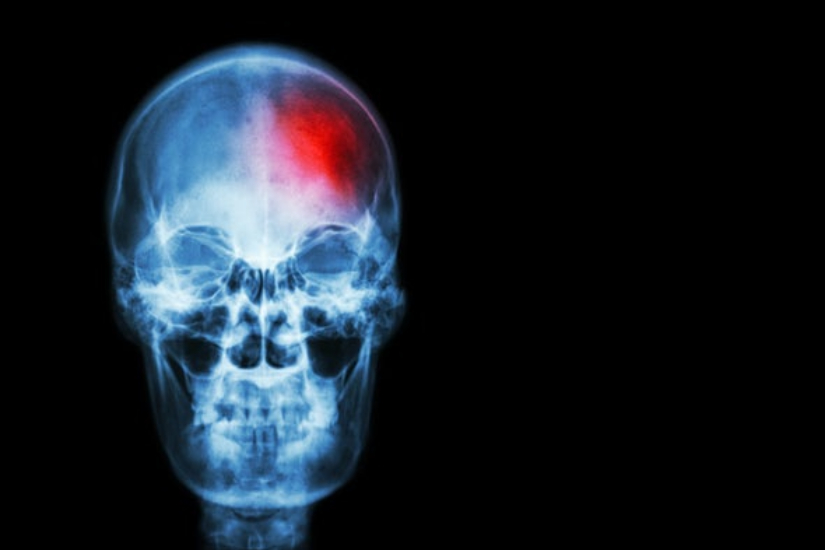

لا تفوتك.. علامة مبكرة غير عادية تظهر قبل السكتة الدماغية

السكتة الدماغية هي حالة طبية طارئة يمكن أن تصبح قاتلة في حالة التأخر في العلاج، وهناك نوعان رئيسيان من السكتة الدماغية؛ ونقص التروية هو النوع الأكثر شيوعًا ويمثل حوالي 87% من إجمالي الحالات.

وتحدث السكتة الدماغية بشكل أساسي عند انسداد الأوعية الدموية التي تزود الدماغ بالدم بسبب جلطة دموية، وهو ما يعطل تدفق الدم إلي الدماغ مما يتسبب في موت الخلايا.

ويمكن أن يكون ضيق الشرايين سببًا آخر للسكتة الدماغية الإقفارية بسبب تصلب الشرايين، وهو مرض تتراكم فيه اللويحات داخل الشرايين مما يتسبب في انسدادها، وتعتبر هذه الحالة خطيرة وتزيد من خطر الإصابة بسكتة دماغية مميتة في المستقبل.

والمشكلة الفعلية هي أن السكتات الدماغية لا تظهر أي أعراض واضحة ويمكن أن يكون من الصعب اكتشافها، لكن توصل الأطباء إلي علامات خفية يمكن الكشف عنها في الأطراف، ويمكن أن يؤدي التعرف عليها واتخاذ التدابير الوقائية في الوقت المناسب إلى إنقاذ حياتك.